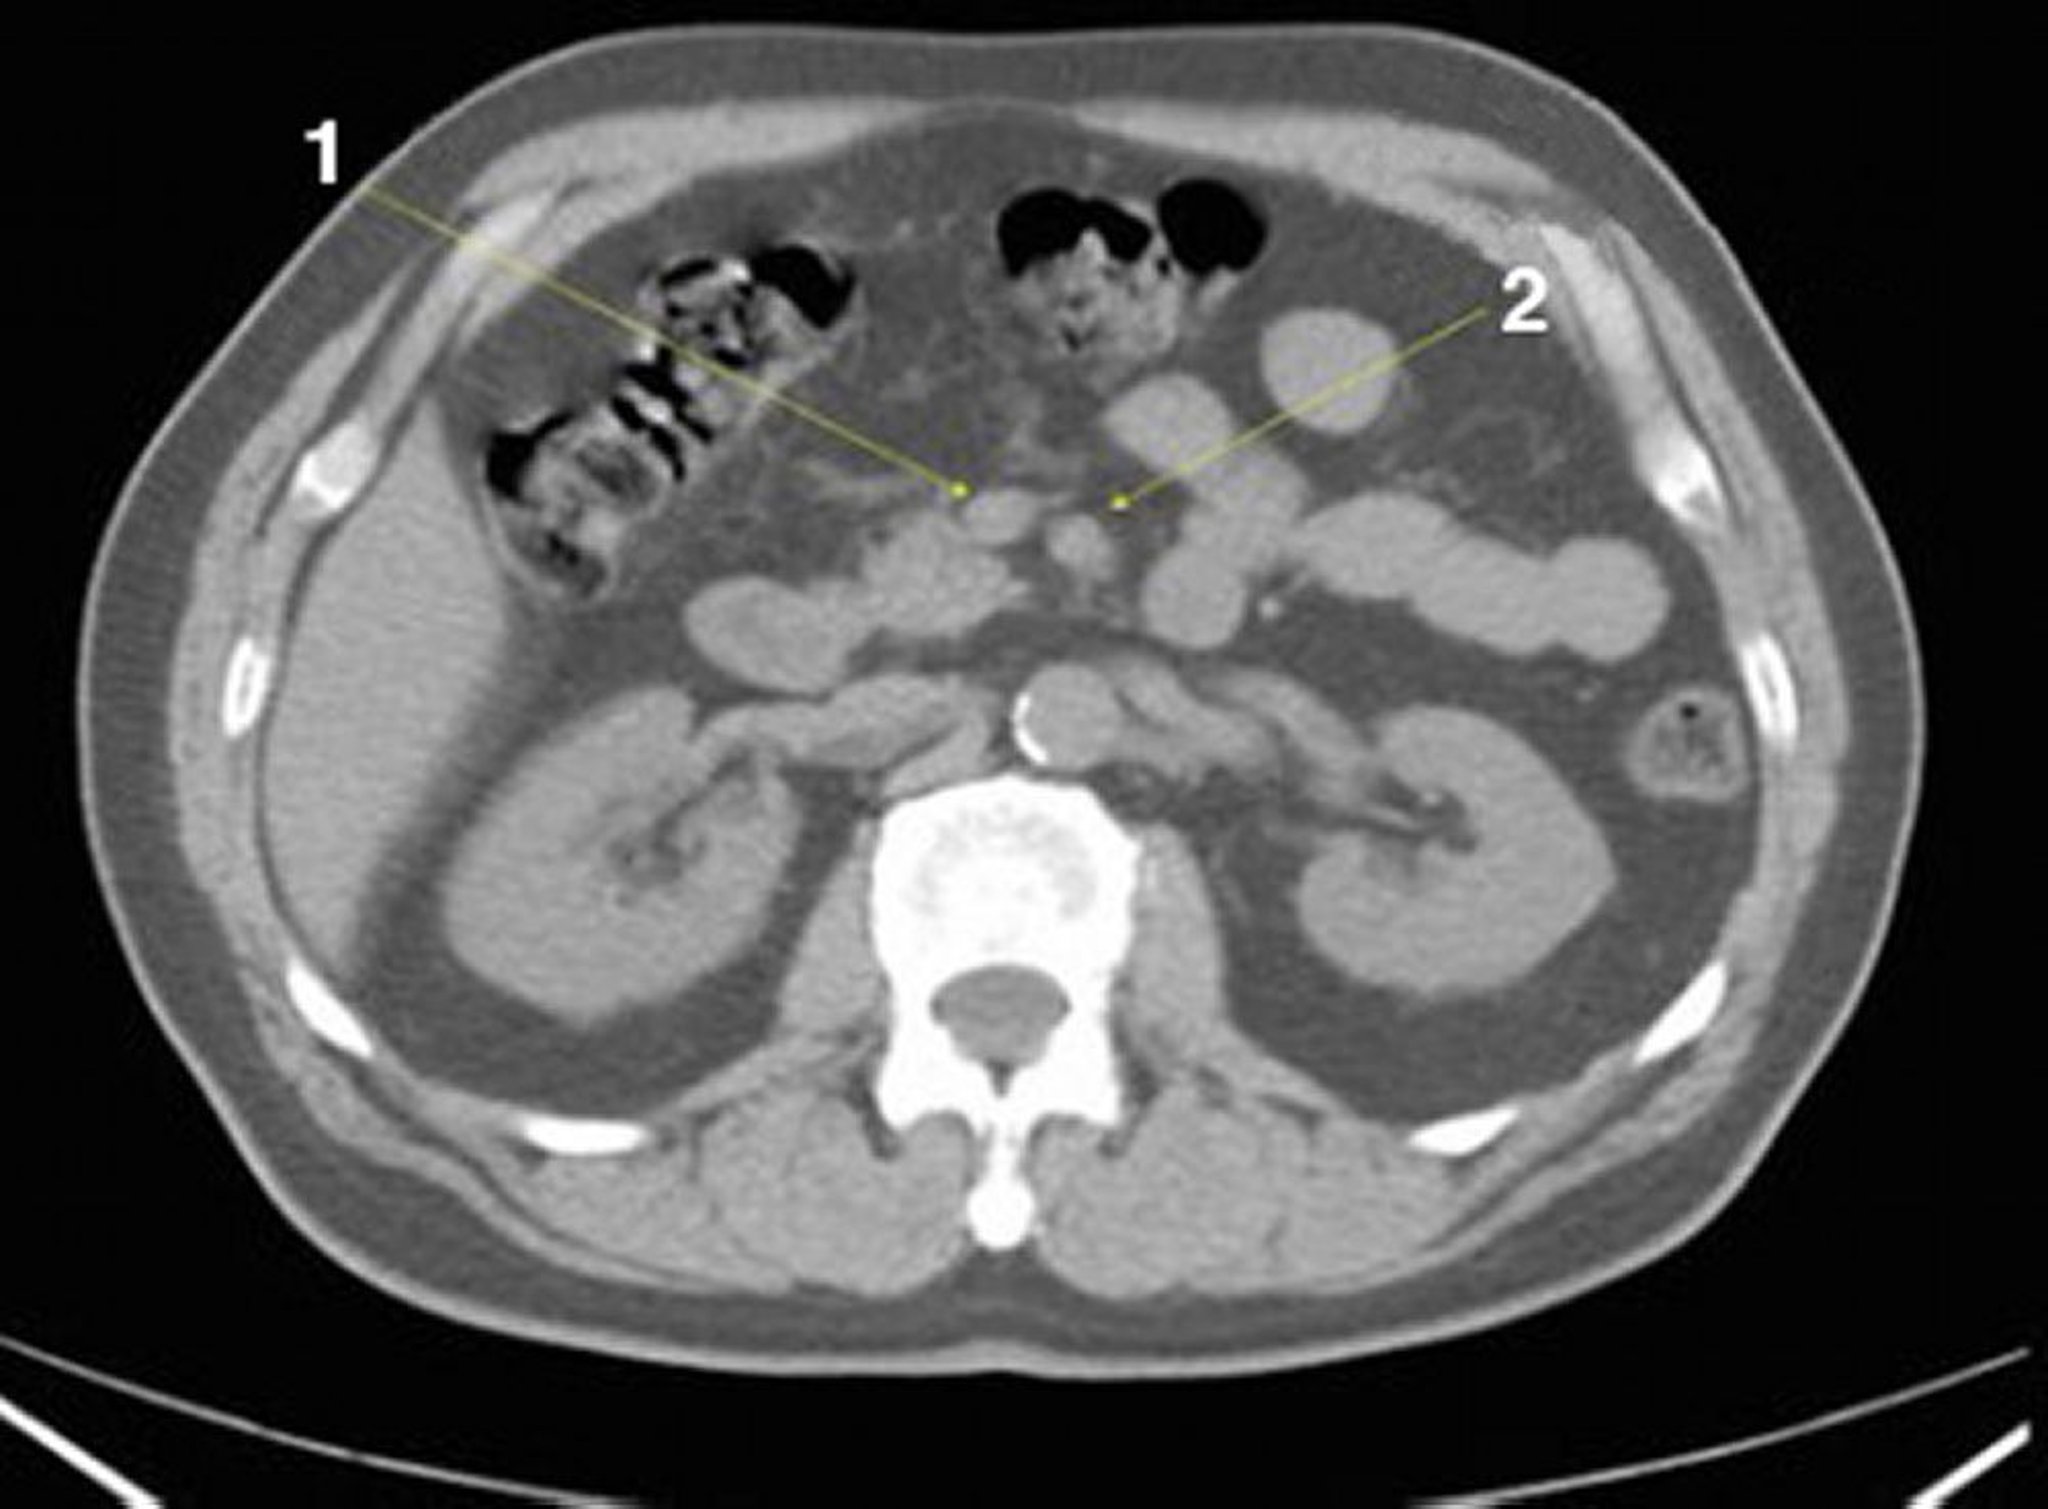

CT-Scan von Abdomen und Becken mit normaler Anatomie ohne Kontrastmittel (Folie 13)

1 = V. mesenterica superior; 2 = A. mesenterica superior.